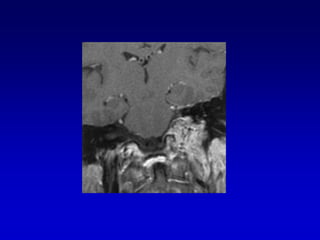

Caso 3TAC RM ANGIO

Caso 3

postembolizacion